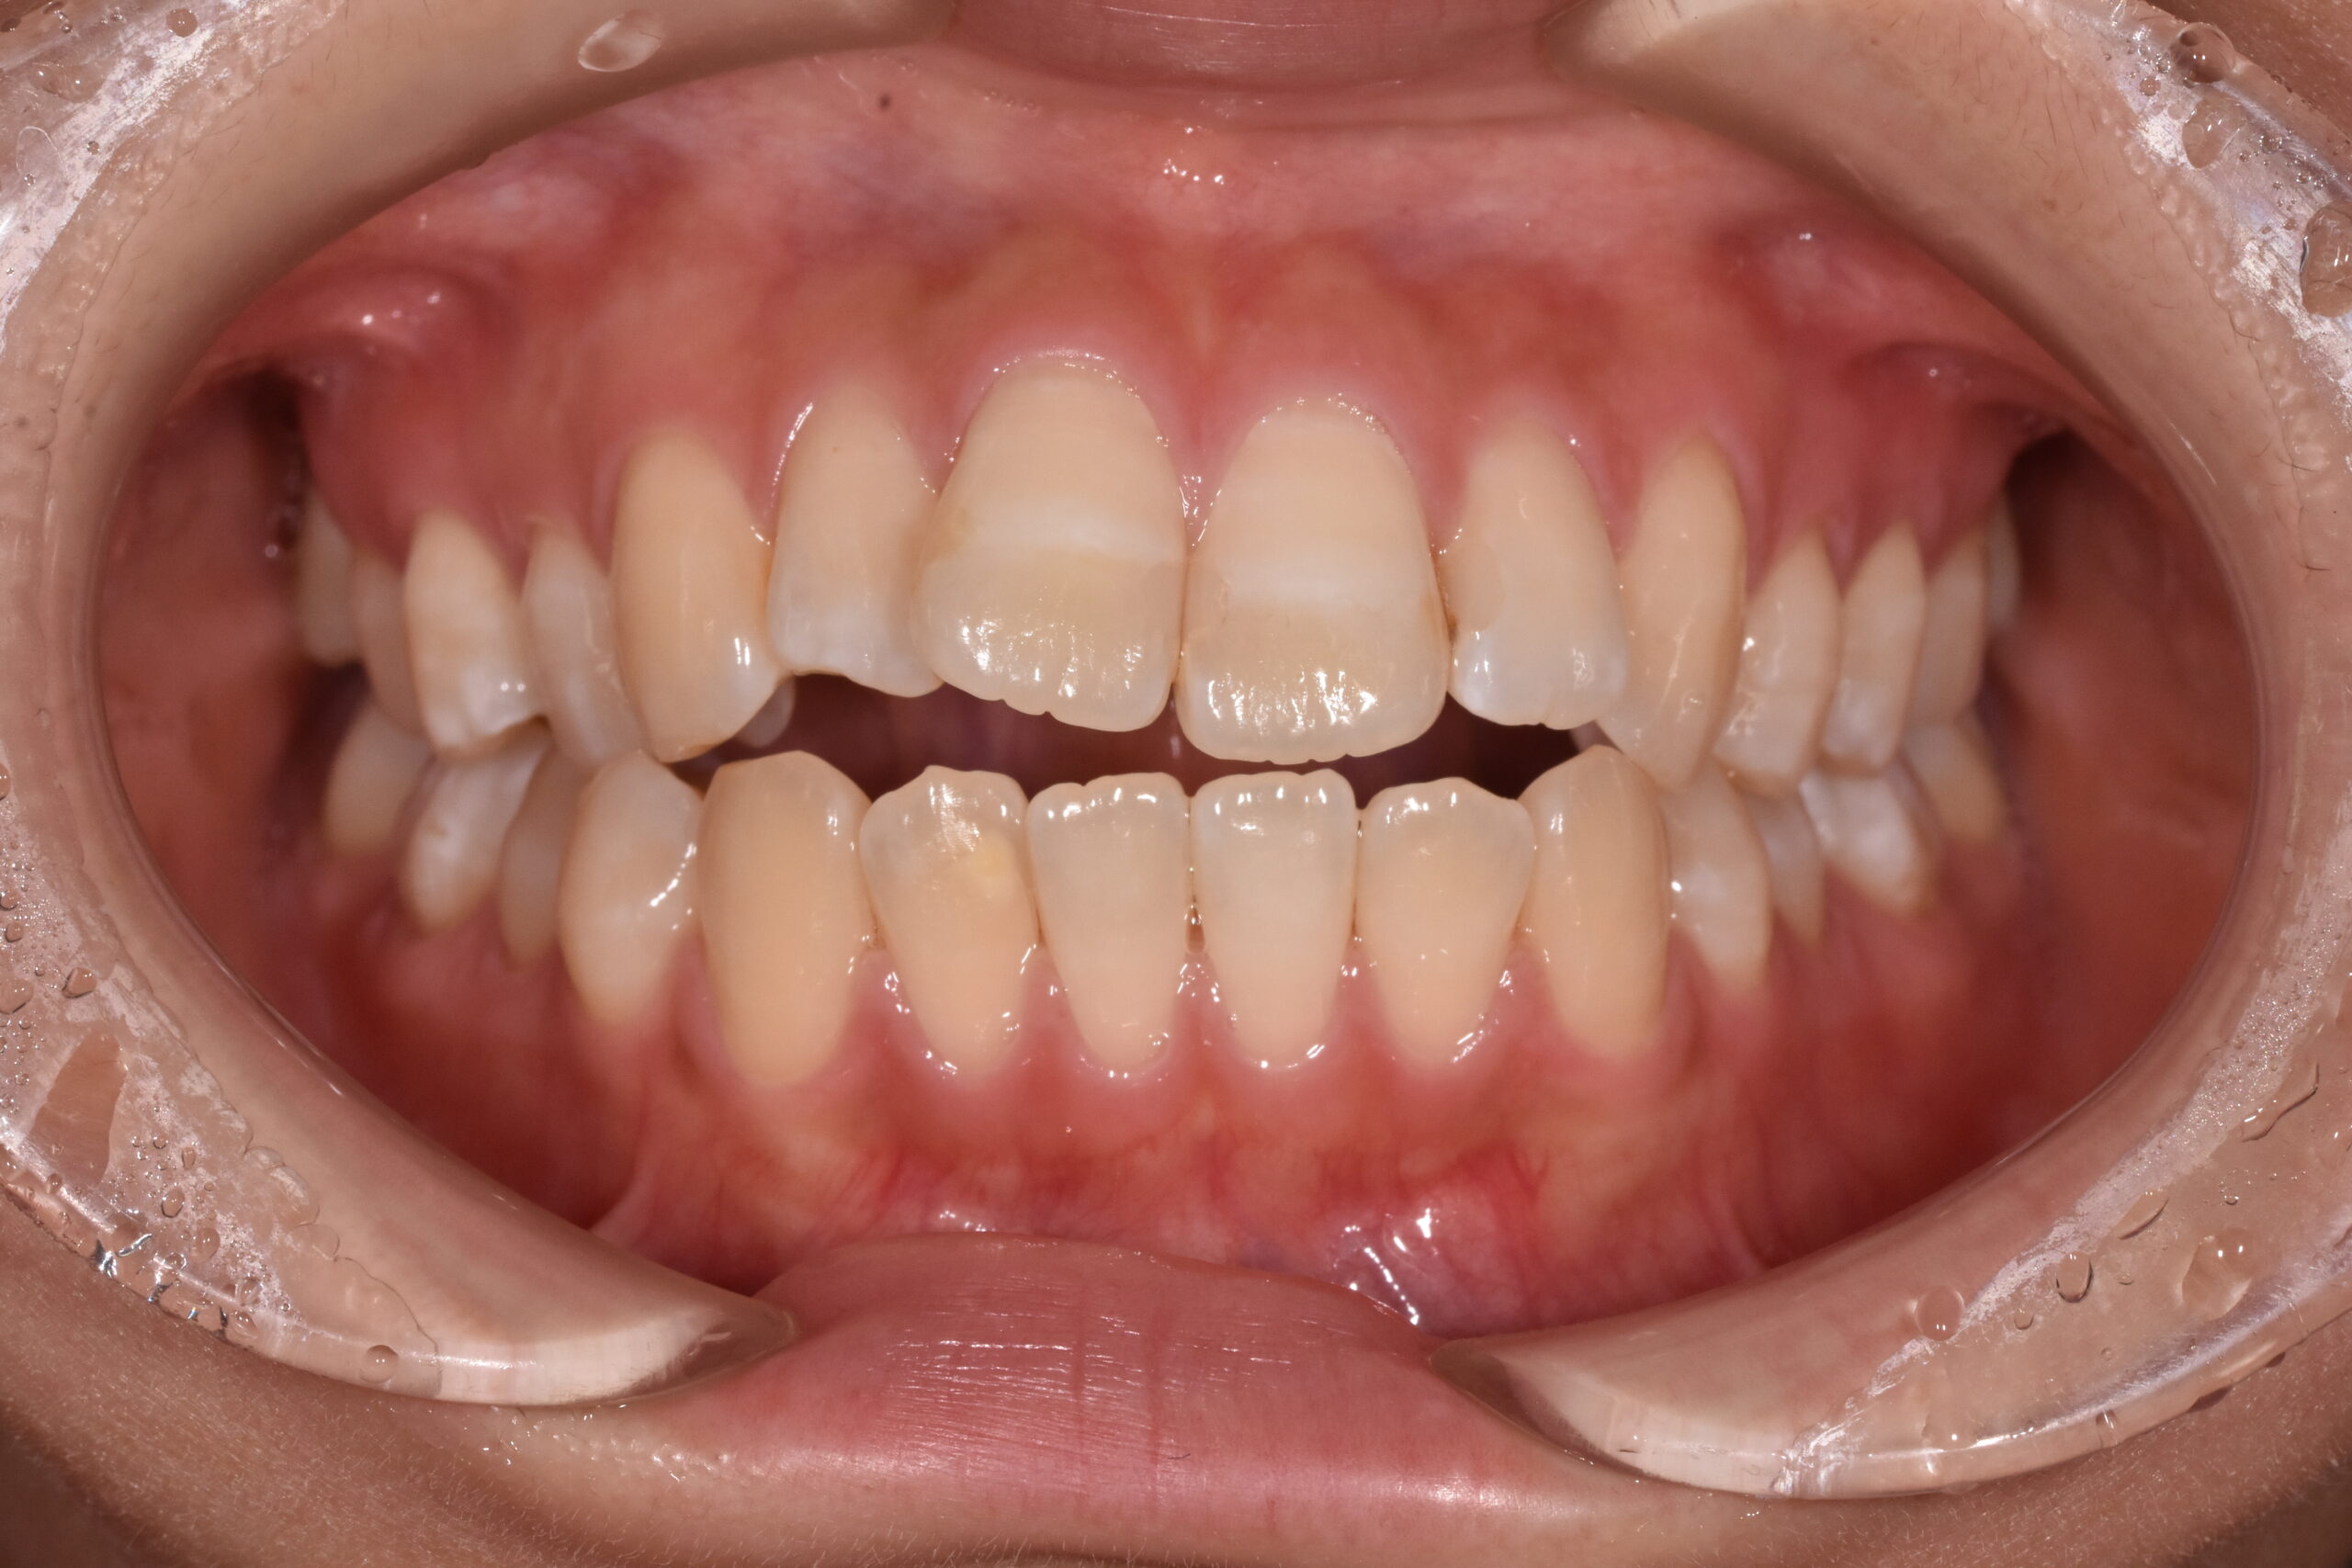

開咬 17歳 女性

治療前

お悩み:

前歯が噛み合わず、食べ物が噛みにくい

状態:

骨格:開咬傾向(前歯が噛みにくいタイプ)

歯並び:前歯が噛み合わない(開咬)+前歯の突出傾向